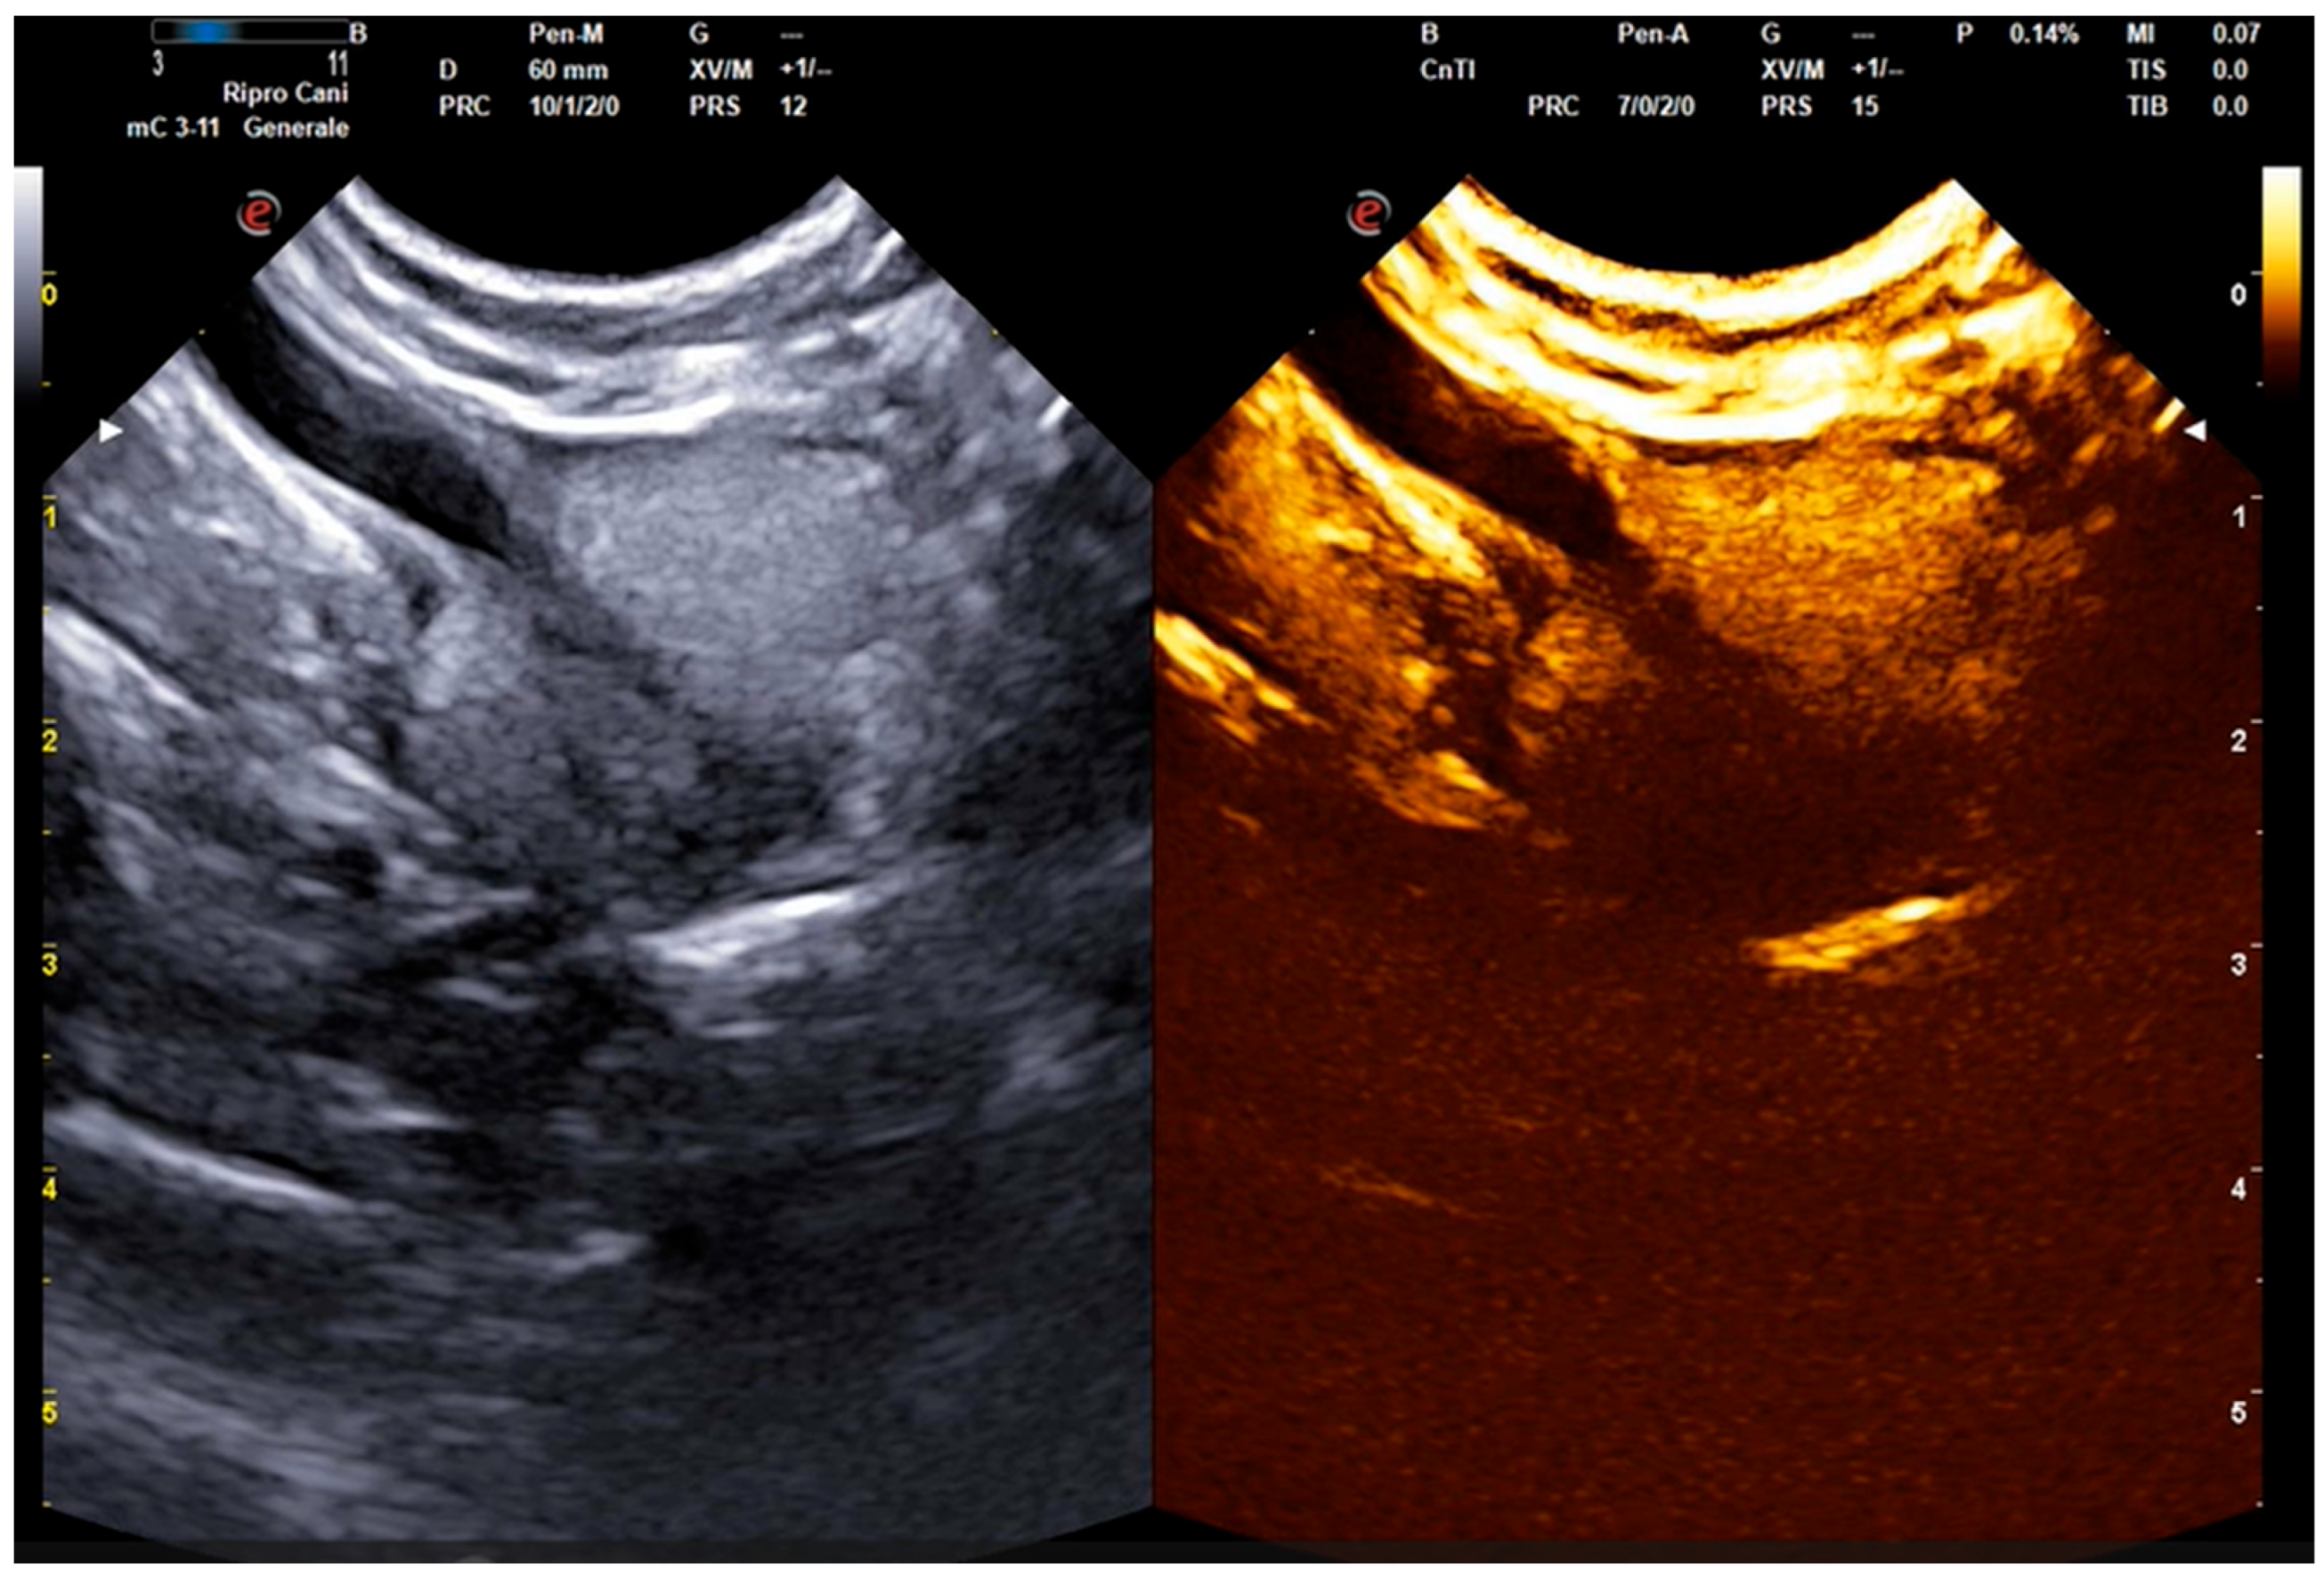

2.2. B-Mode and Contrast-Enhanced Ultrasound Procedures

- Russo, M.; Vignoli, M.; England, G.C.W. B-mode and contrast-enhanced ultrasonographic findings in canine prostatic disorders. Reprod. Domest. Anim. 2012, 47, 238–242. [Google Scholar] [CrossRef] [PubMed]

- Troisi, A.; Orlandi, R.; Bargellini, P.; Menchetti, L.; Borges, P.; Zelli, R.; Polisca, A. Contrast-enhanced ultrasonographic characteristics of the diseased canine prostate gland. Theriogenology 2015, 84, 1423–1430. [Google Scholar] [CrossRef] [PubMed]

- Russo, M.; Vignoli, M.; Catone, G.; Rossi, F.; Attanasi, G.; England, G.C. Prostatic perfusion in the dog using contrast-enhanced Doppler ultrasound. Reprod. Domest. Anim. 2009, 44, 334–335. [Google Scholar] [CrossRef]

- Bigliardi, E.; Ferrari, L. Contrast-enhanced ultrasound of the normal canine prostate gland. Vet. Radiol. Ultrasound 2011, 52, 107–110. [Google Scholar] [CrossRef]

- Vignoli, M.; Russo, M.; Catone, G.; Rossi, F.; Attanasi, G.; Terragni, R.; Saunders, J.; England, G.C. Assessment of vascular perfusion kinetics using contrast-enhanced ultrasound for the diagnosis of prostatic disease in dogs. Reprod. Domest. Anim. 2011, 46, 209–213. [Google Scholar] [CrossRef] [PubMed]